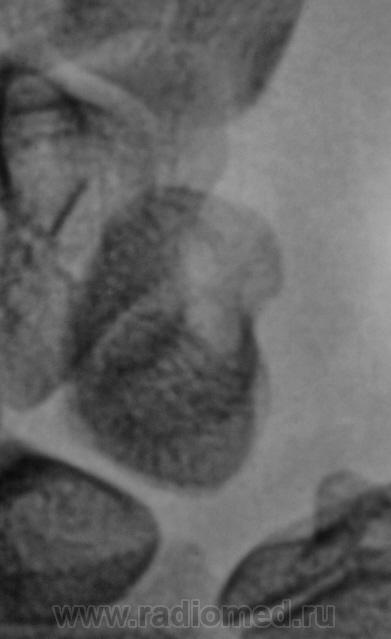

Смущает перестройка структуры костной ткани, помечено стрелками.

111._Struktura..JPG112._Struktura..JPG

Похоже на кисты (здесь - врождённые)

А может ГКО?